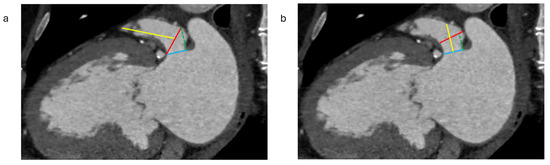

2.1.3. Assessment of the Inter-Atrial Septum

- Fukutomi, M.; Fuchs, A.; Bieliauskas, G.; Wong, I.; Kofoed, K.F.; Søndergaard, L.; De Backer, O. Computed Tomography-Based Selection of Transseptal Puncture Site for Percutaneous Left Atrial Appendage Closure. EuroIntervention 2022, 17, E1435–E1444. [Google Scholar] [CrossRef] [PubMed]

- Nelles, D.; Amli, H.; Sugiura, A.; Vij, V.; Beiert, T.; Nickenig, G.; Kütting, D.; Schrickel, J.W.; Sedaghat, A. The CT Derived Angle between the Transseptal Puncture Site and the Left Atrial Appendage as a Predictor for Complex Interventional Occlusion Procedures. Echocardiography 2023, 40, 1227–1236. [Google Scholar] [CrossRef] [PubMed]

- Hozman, M.; Herman, D.; Zemanek, D.; Fiser, O.; Vrba, D.; Poloczek, M.; Varvarovsky, I.; Obona, P.; Pokorny, T.; Osmancik, P. Transseptal Puncture in Left Atrial Appendage Closure Guided by 3D Printing and Multiplanar CT Reconstruction. Catheter. Cardiovasc. Interv. 2023, 102, 1331–1340. [Google Scholar] [CrossRef]